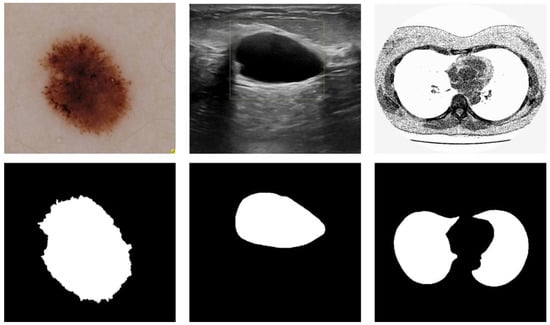

We conducted experiments on three different types of medical imaging datasets to validate the performance of the proposed model. Figure 3 depicts three data samples. The models involved in this paper are implemented based on the deep learning frameworks Pytorch, and the experimental program language is Python. The experiments were run on a dual-core Intel(R) i7-11700 CPU with 32 GB of RAM and an NVIDIA GEFORCE RTX 3080 GPU with 10 GB of RAM. The running platform is Windows 10. The training parameters of the comparison models were kept consistent for the sake of fairness and rationality in the experiment, and the average of five random validation outcomes is the experimental result.

Figure 3. Medical image segmentation: skin cancer lesion segmentation on the left, breast cancer segmentation, and lung segmentation on the right.

Dataset used in this study was from the ISIC Challenge competition in 2018 [25], which is provided by https://www.kaggle.com/datasets/tschandl/isic2018-challenge-task1-data-segmentation/ (accessed on 15 November 2022). It consists of 2594 images and 2594 corresponding ground truth response masks. In this implementation, each sample was rescaled to 256 × 256 pixels.

3.1.2. Breast Cancer Segmentation

The data reviews the medical images of breast cancer using ultrasound scans [26], which is provided by https://www.kaggle.com/datasets/aryashah2k/breast-ultrasound-images-dataset/ (accessed on 15 November 2022). The dataset consists of 780 images with an average image size of 500 × 500 pixels. The experimental data are 647 benign and malignant samples, which are resized to 256 × 256 pixels in this implementation.

3.1.3. Lung Segmentation

The dataset is taken from The Lung Nodule Analysis (LUNA) and The Kaggle Data Science Bowl competition in 2017, which is provided by https://www.kaggle.com/datasets/kmader/finding-lungs-in-ct-data/ (accessed on 15 November 2022). The original image size was 512 × 512. In this implementation, each sample was rescaled to 256 × 256 pixels.